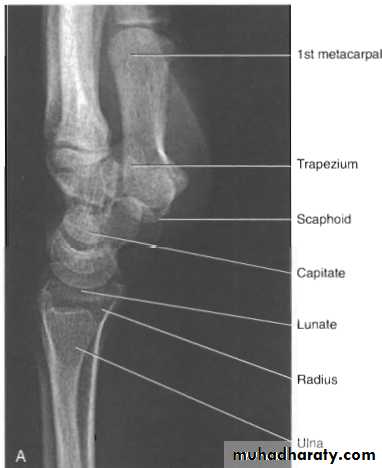

Radiological evaluation

Lateral radiograph